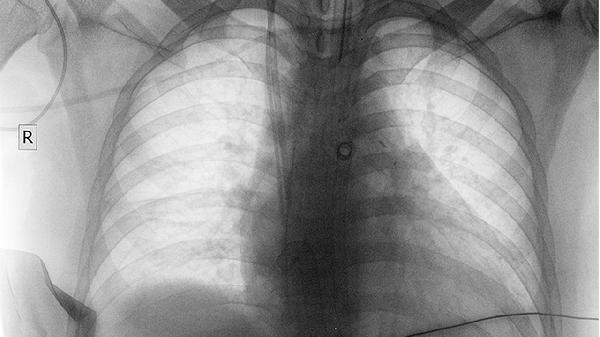

牡蛎、海藻等药物可软化消散肺部良性结节,对直径小于8mm的磨玻璃结节可能有一定抑制作用。用药期间需定期复查CT监测结节变化,发现异常增长应及时调整治疗方案。